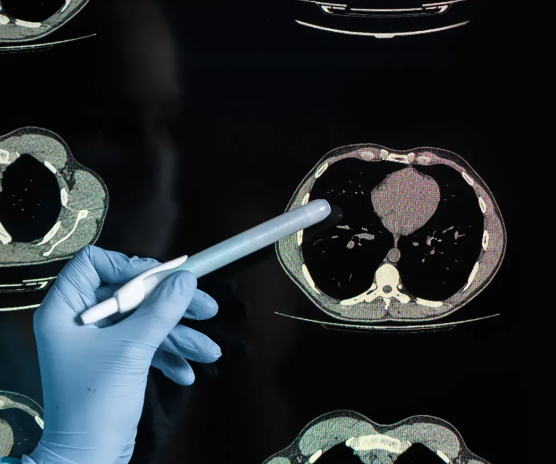

흉부ct로 볼수있는 질환의 범위

흉부CT는 폐를 중심으로 심장, 대동맥, 종격동, 늑막, 흉벽, 기관지까지 폭넓게 확인할 수 있습니다. 단순한 기침이나 호흡곤란부터 흉통, 체중 감소 같은 증상까지 다양한 원인을 탐색하는 데 활용됩니다.

1. 폐질환

흉부CT가 가장 자주 사용되는 영역은 폐입니다. 폐암, 폐결절, 폐렴, 결핵, 기관지 확장증, 폐기종, 폐섬유화증 등 다양한 질환을 세밀히 구분할 수 있습니다. 특히 폐암의 경우 초기에는 증상이 거의 없기 때문에, CT를 통한 조기 발견이 매우 중요합니다. 또한 흡연자의 폐 손상 정도를 평가하거나, 미세한 염증이 반복되는 패턴도 파악할 수 있습니다.

2. 심혈관 질환

흉부CT는 심장의 형태뿐 아니라, 심장 주위의 혈관까지도 함께 관찰할 수 있습니다. 대표적으로 대동맥 박리, 대동맥류, 폐동맥 색전증 같은 질환이 있습니다. 특히 응급 상황에서 흉통 원인을 구분할 때 CT는 빠르고 명확한 판단 근거를 제공합니다.